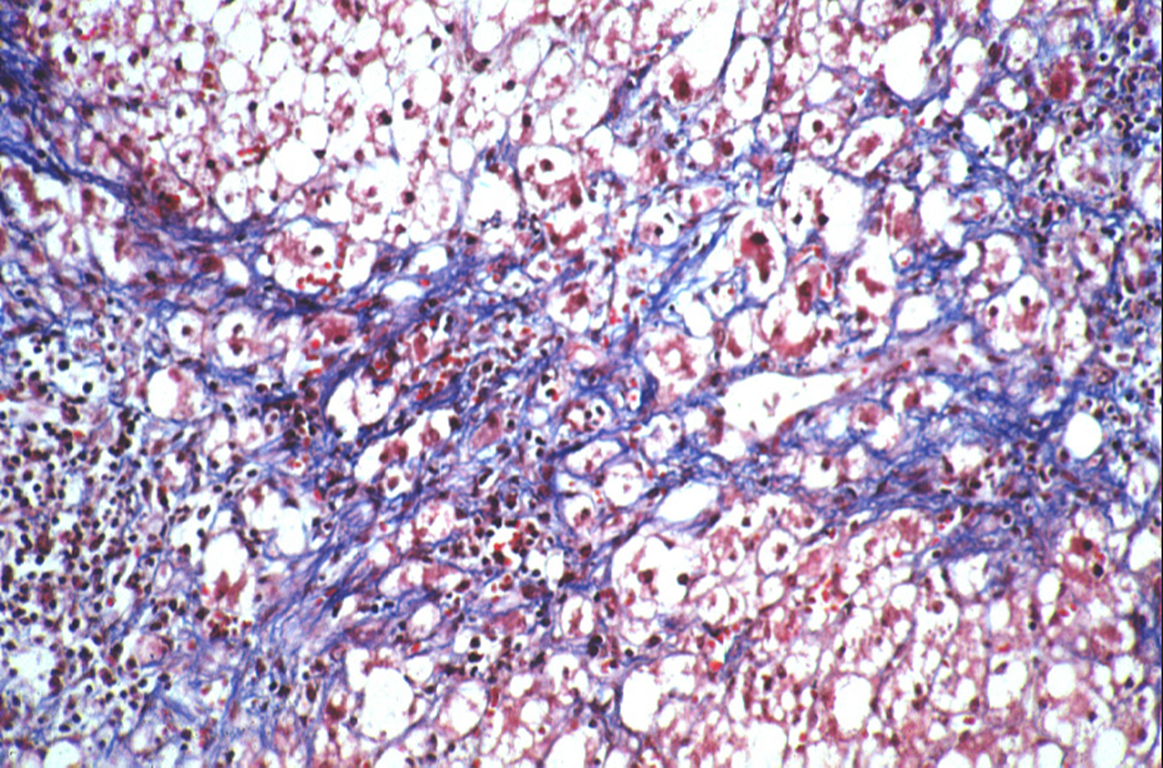

PAS-D positive globules

PAS stain after diastase digestion

alpha 1 antitrypsin globules